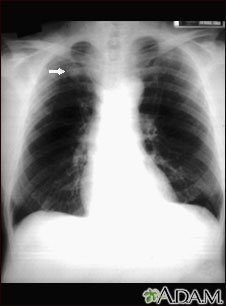

This x-ray shows a single lesion (pulmonary nodule) in the upper right lung (seen as a light area on the left side of the picture). The nodule has distinct borders (well-defined) and is uniform in density. Tuberculosis (TB) and other diseases can cause this type of lesion.